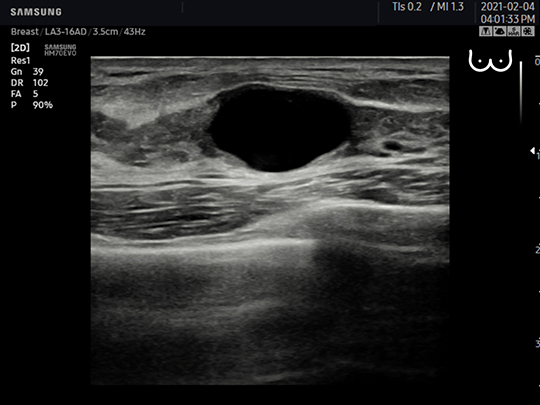

LA3-16AD

- Application: small parts, vascular, musculoskeletal, abdomen, obstetrics, gynecology, pediatric